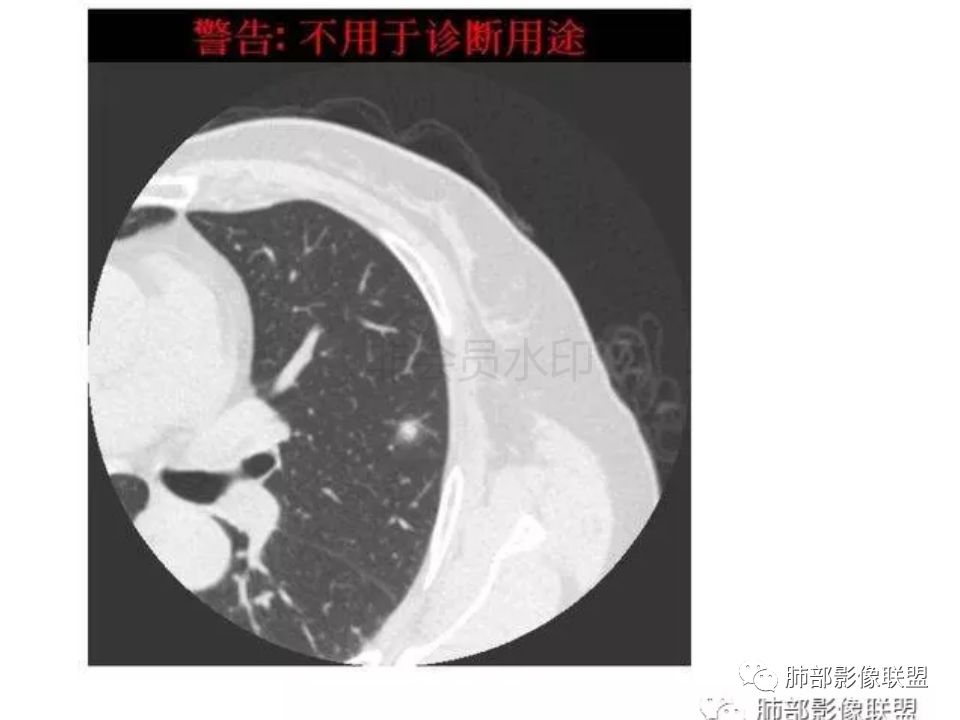

三生石上:支气管有截断,周围有晕,有空泡,腺癌?毛勤香:左肺下叶近胸膜下结节,周围磨玻璃影,边界似稍模糊,局部细支气管截断,实性区和磨玻璃区分界突然,隐约细毛刺,首先考虑感染性,隐球菌?待排腺癌MIA伴肺泡塌陷可能。常规治疗后复查。Coke with ice:IACM-Imaging :孤立胸膜下结节,其内见小泡,周围模糊的晕,晕中软毛刺,近端与血管相连,血管自然通过,气管进入结节内部一半,猜个隐球吧。第二腺癌,建议复查。田园晚风:考虑腺癌紫气东来:左肺上叶,磨玻璃实性毛刺,空泡,支气管截断,腺癌雪颜:左肺上叶结节状密度增高影,周围有晕,感觉周围模糊,有血管进入,里面有空泡征,隐约看到里面有支气管穿过,考虑炎性,隐球菌感染?腺癌待排THINKER:上叶尖后,SPN,有晕,软毛刺,无胸膜凹陷,分叶丶收缩不明显,支气管进入,远端阻塞,首选肉芽肿,PC或炎性结节,有一支血管滋养,鉴别腺癌,增殖性结核结节不支持期:左上肺结节周围有晕 晕中见细软毛刺 首先考虑隐球菌一米阳光:左肺上叶磨玻璃影,空泡,周围毛刺,月牙铲,支气管通过,周围有晕,考虑腺癌我的FY:毛刺,小空泡,磨玻璃考虑恶性崔少钢:小病灶,内有支气管,空泡征,实变不规则,放大了,感觉晕有点偏清,考虑恶性。小病灶里面有支气管是值得高度怀疑的。没有病史。彭君:左肺上叶舌段结节 周围晕模糊 内小支气管扩张 近端与血管相连 自然通过 首先考虑炎性 隐球菌?边缘月牙铲 腺癌待鉴别徐婕:左上肺结节周围有晕 ,晕中见细软毛刺 ,晕边界不太清,先考虑隐球菌张帅:左肺上叶尖后段实性病灶,以细支气管为中心,周围呈毛玻璃样影,并可见密集分布毛刺,内可见支气管征,支气管呈壁呈结节样改变,病灶周围可见血管增粗。考虑 淋巴瘤?鉴别隐球。张延军:混合型磨玻璃结节,伴毛刺,支气管截断,空泡,考虑浸润性腺癌,建议抗炎治疗后复查XGQ:支持隐球春秋:结节伴晕征,晕中毛刺,相邻小支气管近端进入,远端阻塞,近端血管相连,首先考虑隐球菌王秀仙:左肺上叶混合型磨玻璃结节,支气管截断,空泡,有毛刺,考虑浸润性腺癌,建议抗炎治疗后复查玫:左肺上叶磨玻璃结节影,薄扫见长短不一毛刺,有空泡,病灶边缘见晕征,考虑小腺癌可能,不除外炎性结节。zyf:左肺下叶近胸膜下结节,周围有晕,细软毛刺,有支气管进入,实性区和磨玻璃区分界明显,首先考虑感染性,隐球菌?查隐球菌荚膜抗原!RockJ-ason:考虑隐球采莲:左上肺靠近胸膜下实性结节影,边缘模糊,周围有晕及晕中毛刺,支气管进入通畅,有小空泡。考虑炎性病变,隐球可能性大。鉴别结核。Harvey:左肺下叶舌部小结节,边缘见磨玻璃影,边界欠清,内见支气管、管壁不光整,偏向恶性。鉴别隐球菌lmg:左肺上叶混合小结节,有晕,边界模糊,有有小毛刺。考虑炎性病变,隐球收选。AIS并肺泡塌陷带排。山河:倾向腺癌红日东升:GGO边界似清非清,内部好像不是小空泡,是小支气管腔,倾向炎性病变,常规抗炎复查除外腺癌,尤其粘液腺癌。

我怎么感觉支气管是通的,周围的晕又比较软,我考虑炎性病变,隐球菌可能大(如下图)

隐球菌感染孤立病灶与肺腺癌结节在影像上有时难分彼此,尽管隐球菌胸膜下更常见。

1.隐球菌病灶往往是实性密度结节为主伴周边边界不清楚的晕,有时可见晕内细软毛刺。

2.隐球菌病灶形态往往圆钝柔和,缺乏收缩能力,很少出现腺癌的那种胸膜牵拉和棘状突起。

3.病灶内支气管安然无恙隐球菌病灶更加多见